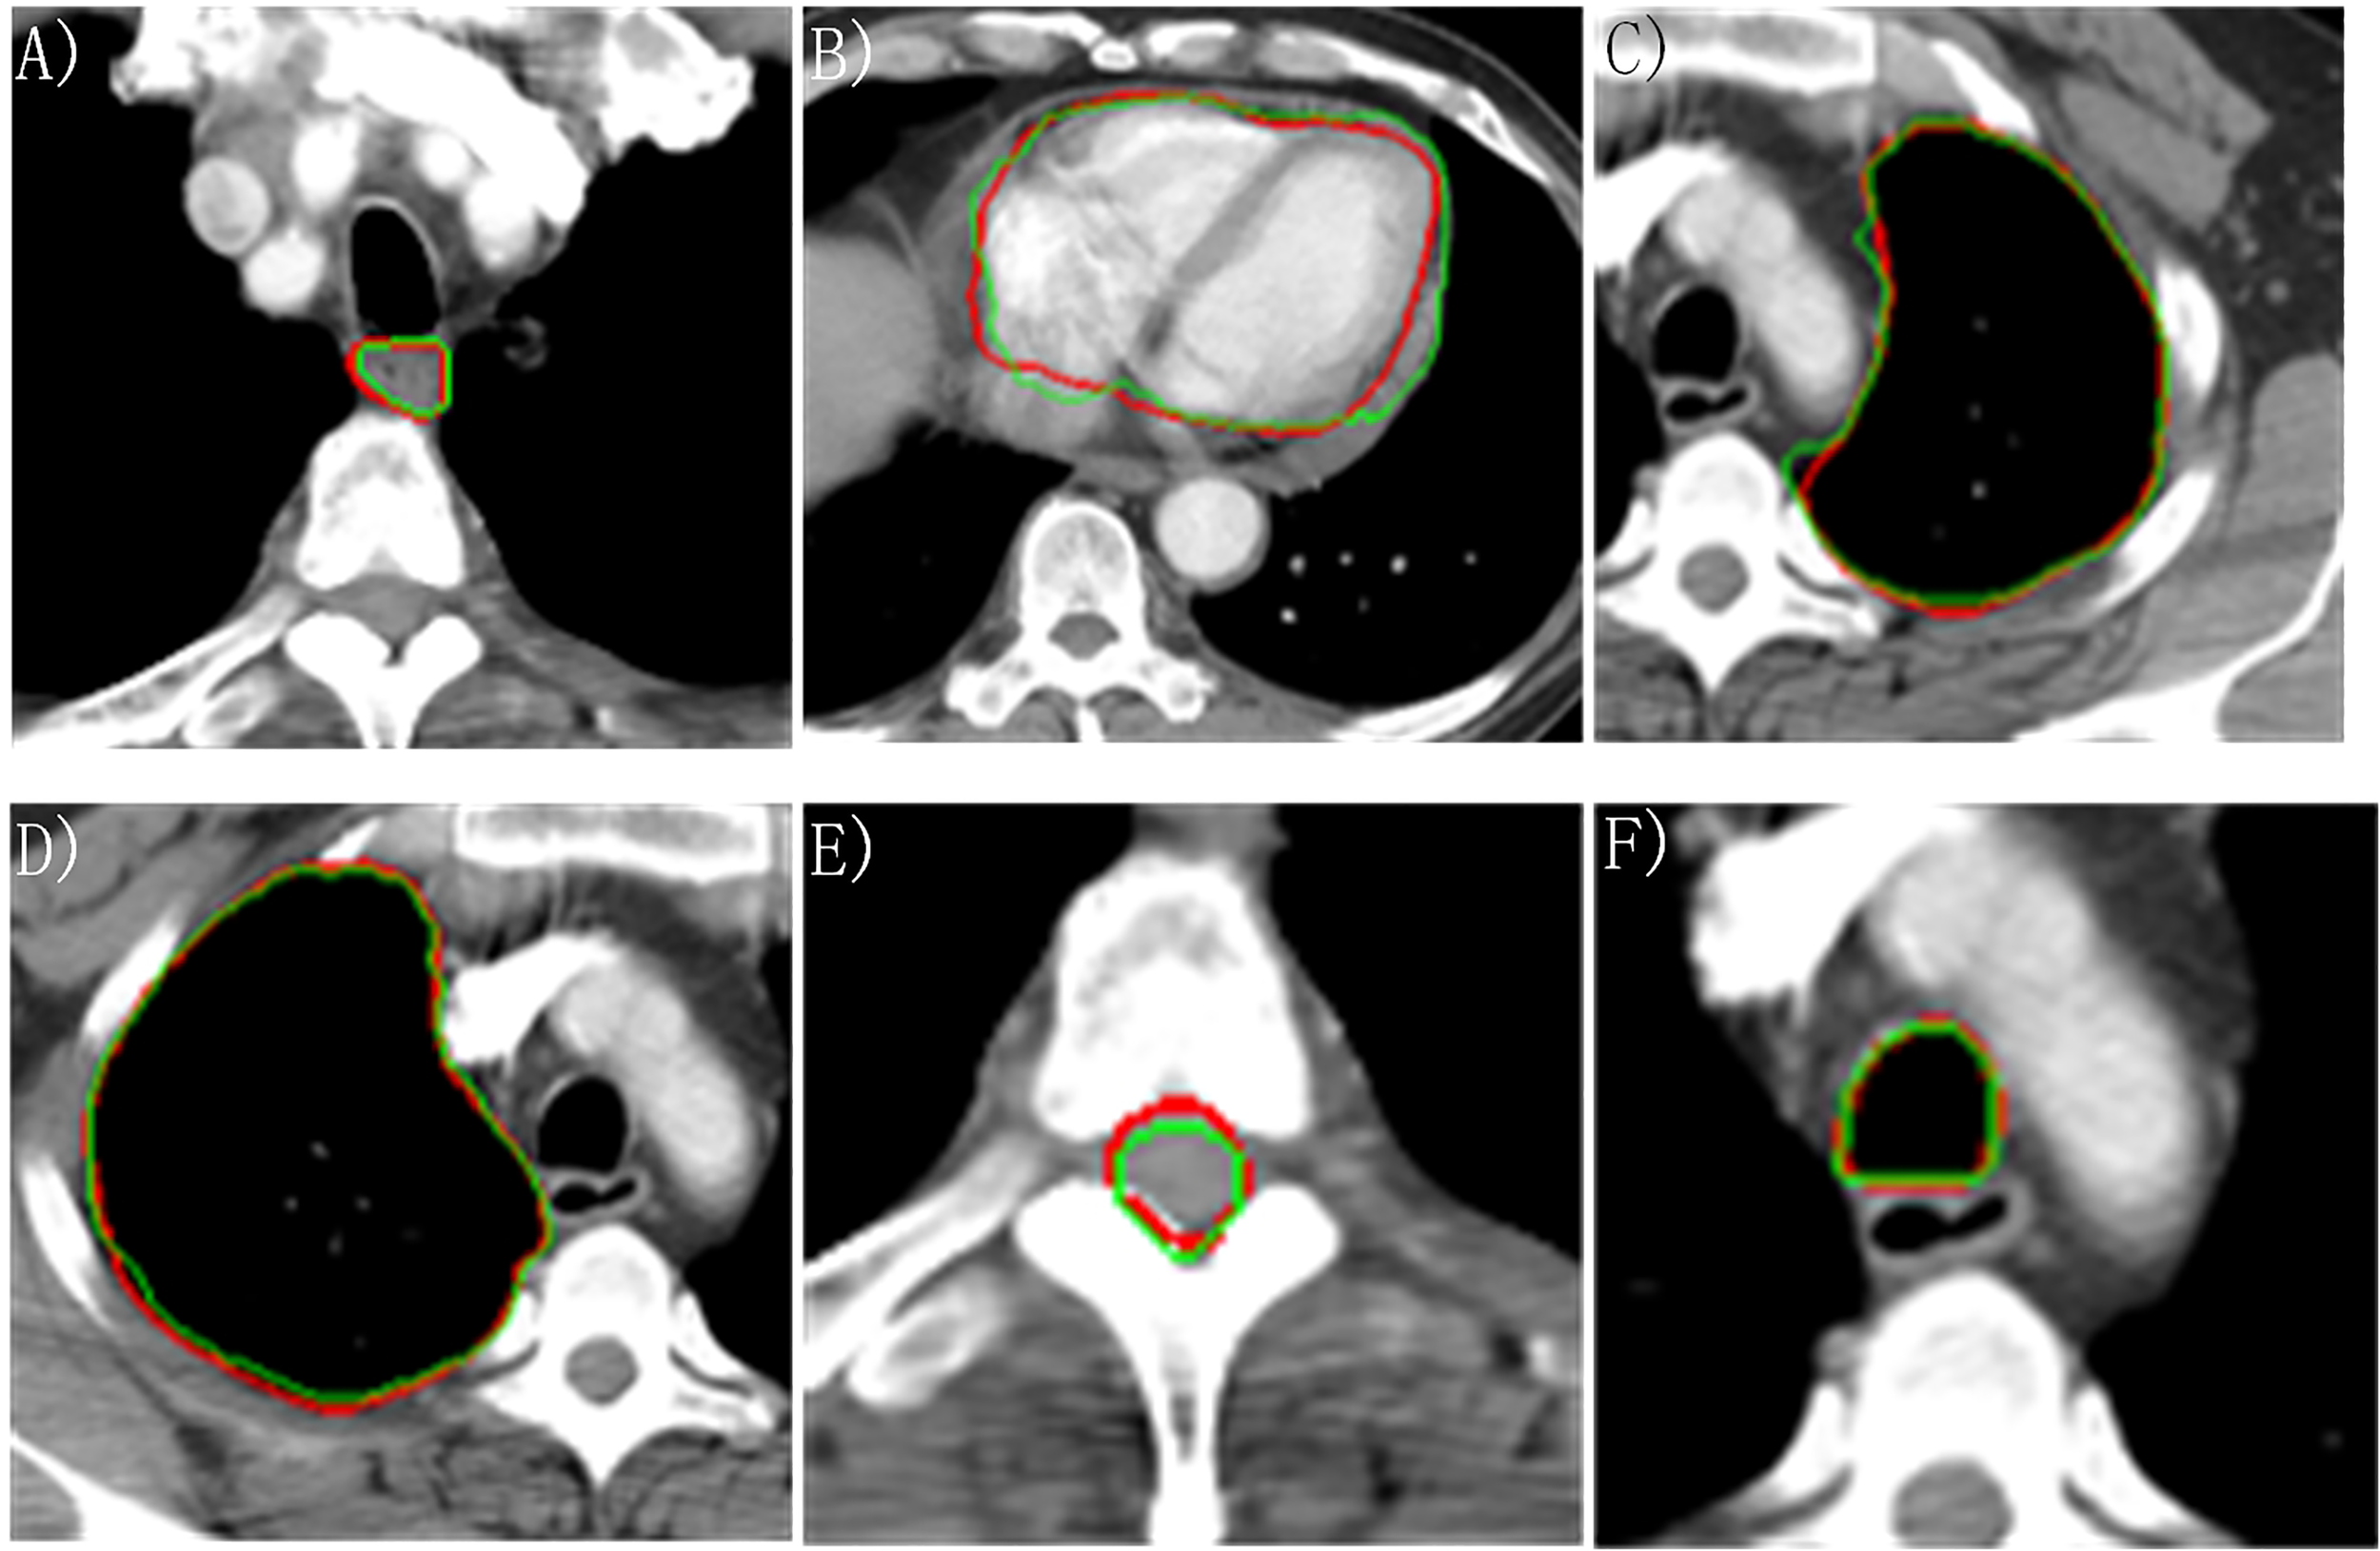

The DSC, HD95, and ASD based on the proposed two-step segmentation model and U-Net are listed in Table 2. Figure 3 demonstrates the comparison of the results between manual and automatic segmentation based on the proposed model for a typical patient. Moreover, Figure 4 specifically shows the DSC, HD95, and ASD of the esophagus in the testing set.

Figure 3

Manually and automatically segmented organs at risk based on the proposed model. Red line: manual contour; green line: automatic contour. (A) Esophagus; (B) Heart; (C) Left lung; (D) Right lung; (E) Cord; (F) Trachea.